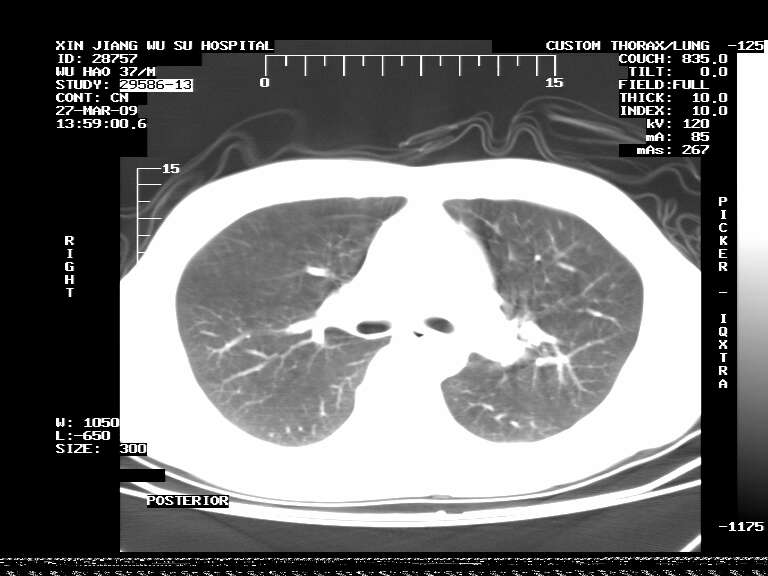

男,37岁,体检胸透发现阴影。

患者体检发现 无症状 左肺下叶占位,边缘模糊,可见血管聚束、分叶、胸膜牵拉,增强呈不均匀性强化。 首先考虑左肺下叶周围型肺癌,建议穿刺活检。

患者体检发现 无症状 左肺下叶占位,边缘模糊,可见血管聚束、分叶、胸膜牵拉,增强呈不均匀性强化。 首先考虑左肺下叶周围型肺癌,建议穿刺活检。支持!

左肺下叶见一结节病变,边缘欠清不光滑,与胸膜粘连且胸膜局限性增厚,注药后呈环形强化,动脉期壁呈明显点环状强化,静脉期壁强化减低,中心密度低无强化,灶周无明显的卫星灶和水肿区(晕征)---考虑周围性肺癌,不除外感染性病变,建议穿刺活检。

左肺下叶结节影.密度不均,边缘不规则.周围少许渗出.考虑感染性病变.结核?肿瘤待排.

左肺下叶软组织病灶,密度较高,内见点状钙化,其周围见子灶,邻近胸膜扁平样增厚.c+病灶强化明显,中心强化弱.诊断:左肺下叶结核瘤.